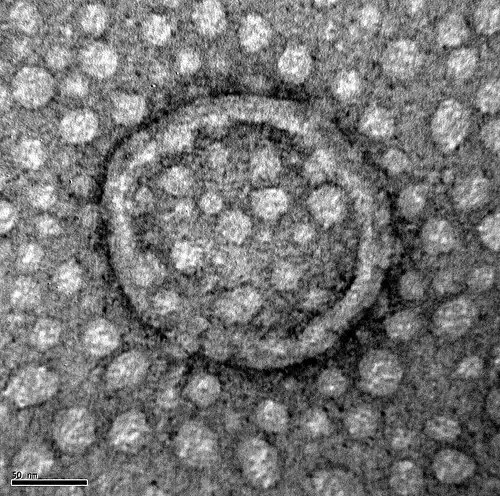

وزیکول یا ریز کیسه یک حباب درون یا بیرون سلول است که حاوی مایع یا سیتوپلاسم بوده و پوستهٔ آن یک غشای دولایه لیپیدی است. به طور دقیق تر وزیکول یک کیسهٔ پوسته مانند درون سلولی می باشد که به ترابری و اندوختن مواد می پردازد. وزیکول دست کم از یک لایهٔ دوجدارهٔ فسفولیپیدی تشکیل شده است.

انواع مختلفی از وزیکول وجود دارد مثل: لیزوزوم، وزیکول انتقالی، وزیکول تراوشی و… وزیکول ها در بخش های مختلفی از سلول مانند شبکهٔ آندوپلاسمی، دستگاه گلژی، پوسته سلول و… ساخته می شوند. وزیکول هایی که به صورت مصنوعی نیز ساخته می شوند. لیپوزوم ها ومیسل و نیوزوم ها از این دسته هستند، اندازهٔ این وزیکول ها بر اساس کاربردشان اندازه های مختلفی دارند به عنوان مثال لیزوزوم از وزیکول انتقالی اندازه بزرگ ترین دارد.